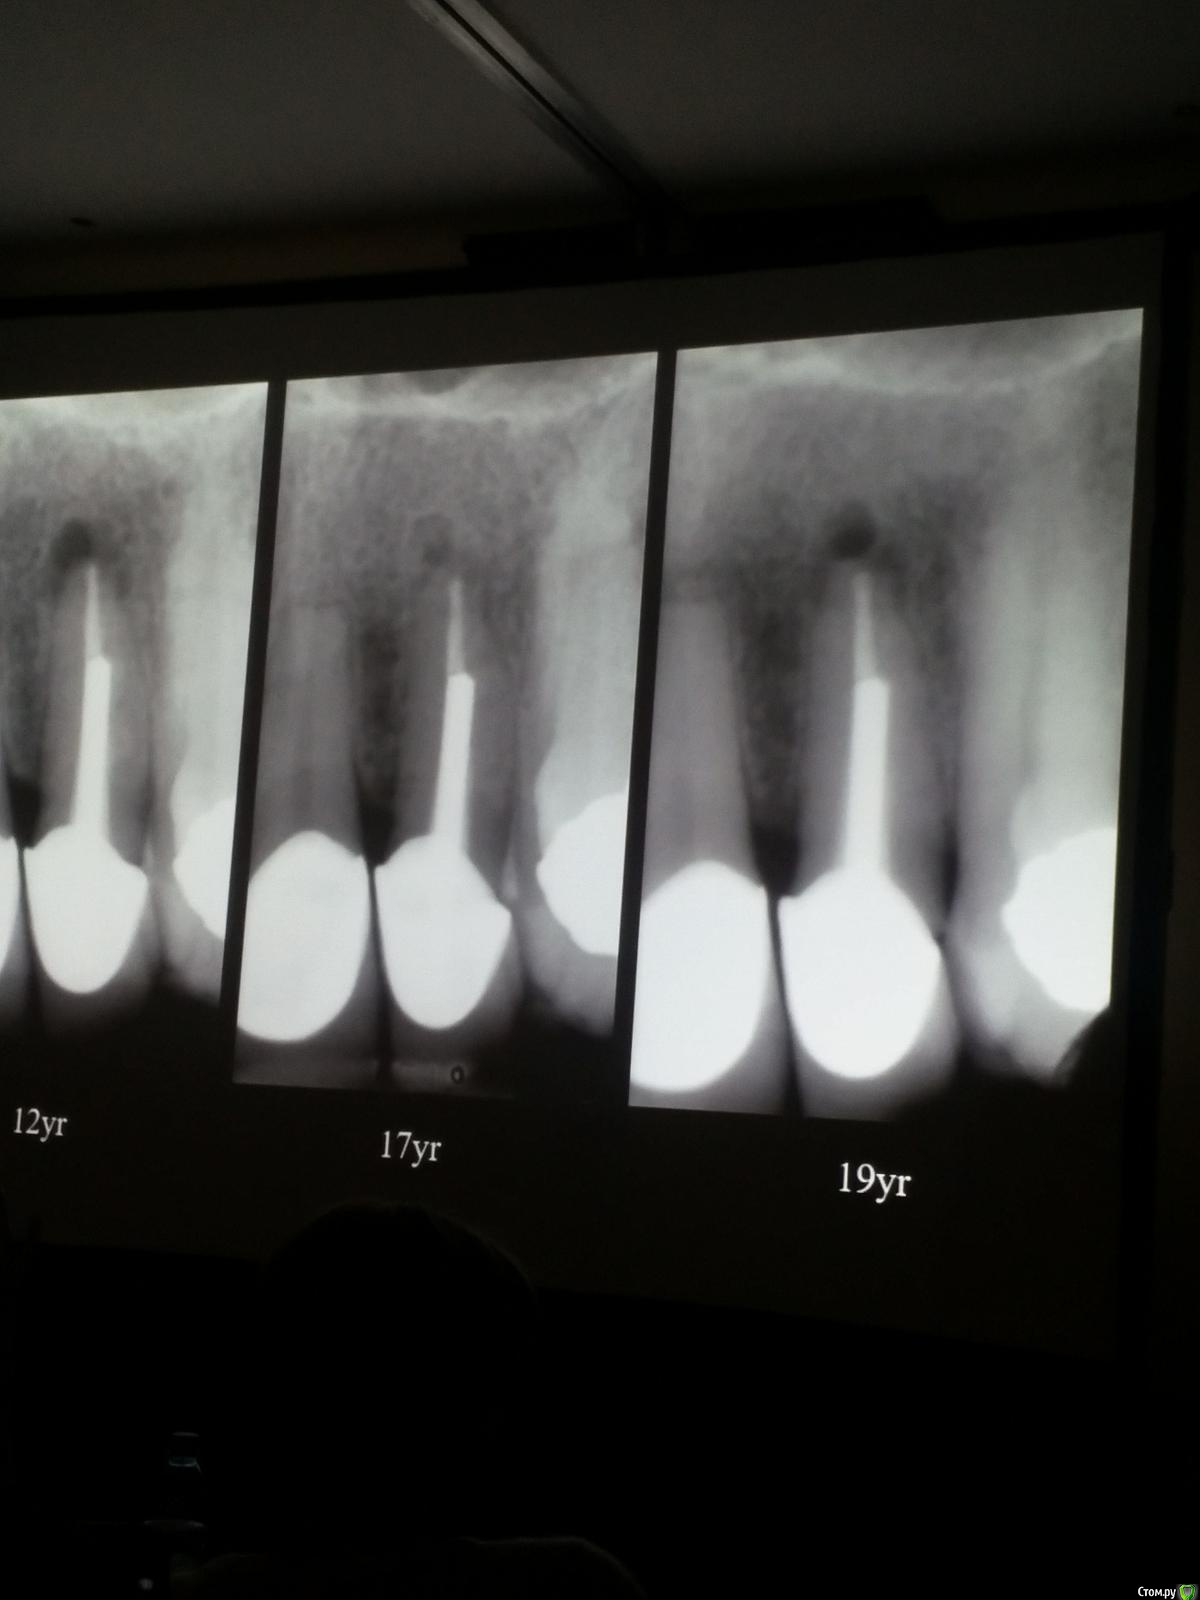

Популярный пост Kolchanov Опубликовано 11 марта, 2017 Популярный пост Поделиться Опубликовано 11 марта, 2017 (изменено) Товарищи, скажу я вам...........Вкратце. Может я где-то что-то и приврал, надеюсь, кто еще был, поправят. Честно говоря немного прибалдел от уровня Доктора. Очень, очень высоко! Приедет еще раз, пойду еще. 1) Фиссуры зондирует острым зондом и выпиливает все дотла. По факту у него уже пломбы, а не герметизация.2) Bite-wing у первичных пациентов всегда.3) Если кариес диагносцирован, то лечить его, пофиг какой он там. Эмали, дентина…4) Препарирует до твердого (или до вскрытия J ). CAD, СID… в топку. Кариес маркером не пользуется, проверяет острым зондом/экскаватором. Вычищает все дотла. Считает, что даже небольшое количество бактерий в дентине под пломбой вызывают хроническое воспаление в пульпе. С его слов у него на контроле где-то 500 вскрытий, не удивительно при таком подходе к очистке.5) Тщательная изоляция. Коффер порвался – меняет. Большое значение герметичности реставрации. под замену6) Критерии обратимости и необратимости.Гистологически, обратимый тот, что без абсцессов в пульпе, но клинически это понять нельзя, только предположить.Здесь был бы обратимый, если бы не удалил. Нет микробов в пульпе. Линия - граница обработки.Покрытие 27 лет назад. Dycal, СИЦ, композит. От дайкала одно воспоминание.7) Вскрылись. Размер перфорации, возраст и прочее не играют роли, важно только состояние пульпы, т.е. диагноз.Примеры перфораций.8) Кровотечение останавливает стерильным ватным шариком. Если останавливается, то покрытие, если нет, то пульпотомия или пульпэктомия.9) Использует гидроокись кальция (порошок), перекрывает Dycal или СИЦ. Потом восстановление Нередко под IRM, потом все убирает (через пару-тройку месяцев) и смотрит, что получилось. Порой приходится повторять! Использует и МТА, его тоже убирает.10) Наблюдение 6мес, 1 год, 2…. Все может провалиться и через месяц и через 24 года.Примеры проваловНиже - 24 года спустя появилась дуля. 11) Неравномерная облитерация полости зуба на RG (после покрытия) – признак текущего хронического воспаления, где-то остались микробы. Рекомендует эндо.12) Мостик который образуется – это не дентин! И одонтобласты не регенерируют и новые не образуются. Что это такое он и сам не знает, но раз это твердые ткани, то и наплевать.Вот фиолетовое это дентинные опилки вмурованные в розовую ткань бог знает кем сформированную.13) Пульпотомия в зубах с несформированной верхушкой и в сформированных, при подозрении на частичное поражение коронковой пульпы. Иссекается стерильным алмазным бором часть пульпы, гидроокись, временная пломба на 90 дней, после повторное раскрытие, оценка результата, восстановление в случае формирования твердых тканей. Гипохлоритом можно мыть, можно не мыть, если мыть, то 0,5-1%.14) В апикальной части пульпа чаще витальна, чем нет.15) Периапикальные поражения возникают по причине поступления токсинов микробов с током крови, а не самих бактерий.16) За апикальные расширения в полностью некротических случаях. Надо механически отодрать биопленку и срезать инфицированный дентин. На ирриганты надежды мало.17) Биопленка на поверхности в 6% случаев.Синенькие пид@расы18) Обработку проводить нежно, краун-даун. Чередовать с H-файлом, чтобы посмотреть докуда распространяется некроз.19) Патенси в витальных кейсах не колоть, сохранять витальную пульпу в констрикции!Формирование еще большего сужения в констрикции за счет сохранения витальной пульпы. Изменено 11 марта, 2017 пользователем Kolchanov 31 Ссылка на комментарий

zubolekar163 Опубликовано 10 апреля, 2017 Поделиться Опубликовано 10 апреля, 2017 (изменено) Больше всего в вебинаре Рикуччи меня убило то что он ЦОЭ силером пользуется.А кое кто нам тут про биокерамические силеры рассказывает Изменено 10 апреля, 2017 пользователем zubolekar163 Ссылка на комментарий